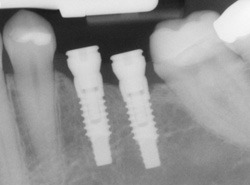

Implants are versatile. If you are only missing one tooth, one implant plus one replacement tooth will do the trick. If you are missing several teeth in a row, a few strategically placed implants can support a permanent bridge (a set of replacement teeth). Similarly, if you have lost all of your teeth, a full bridge or full denture can be permanently fixed in your mouth with a strategic number of implants.

- Computer-Enhanced Treatment Planning: We have special software on our computer that allows us to evaluate your dental CT scan in three dimensions for bone quality, bone quantity, and bone location, enabling the best possible placement of your dental implants. This also allows us to work closely and smoothly with your restorative dentist to ensure an ideal result where your dental implants are concerned.